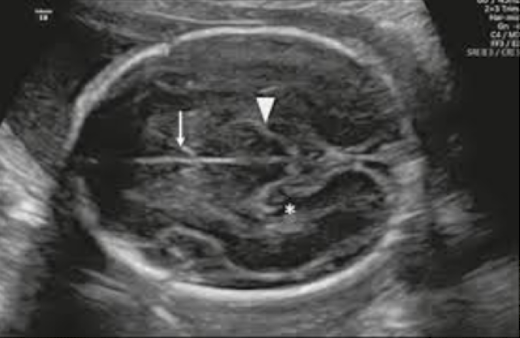

Cisterna Magna

fluid filled cavity in the posterior skull

posterior to the cerebellum and anterior to the occipital bone

normal 3-10mm

measure after 16w

nuchal fold

skin that covers the inferior mid occipital bone and posterior neck

normal measurement is 18w-20w: <6mm

measure outside occipital bone outer skin edge